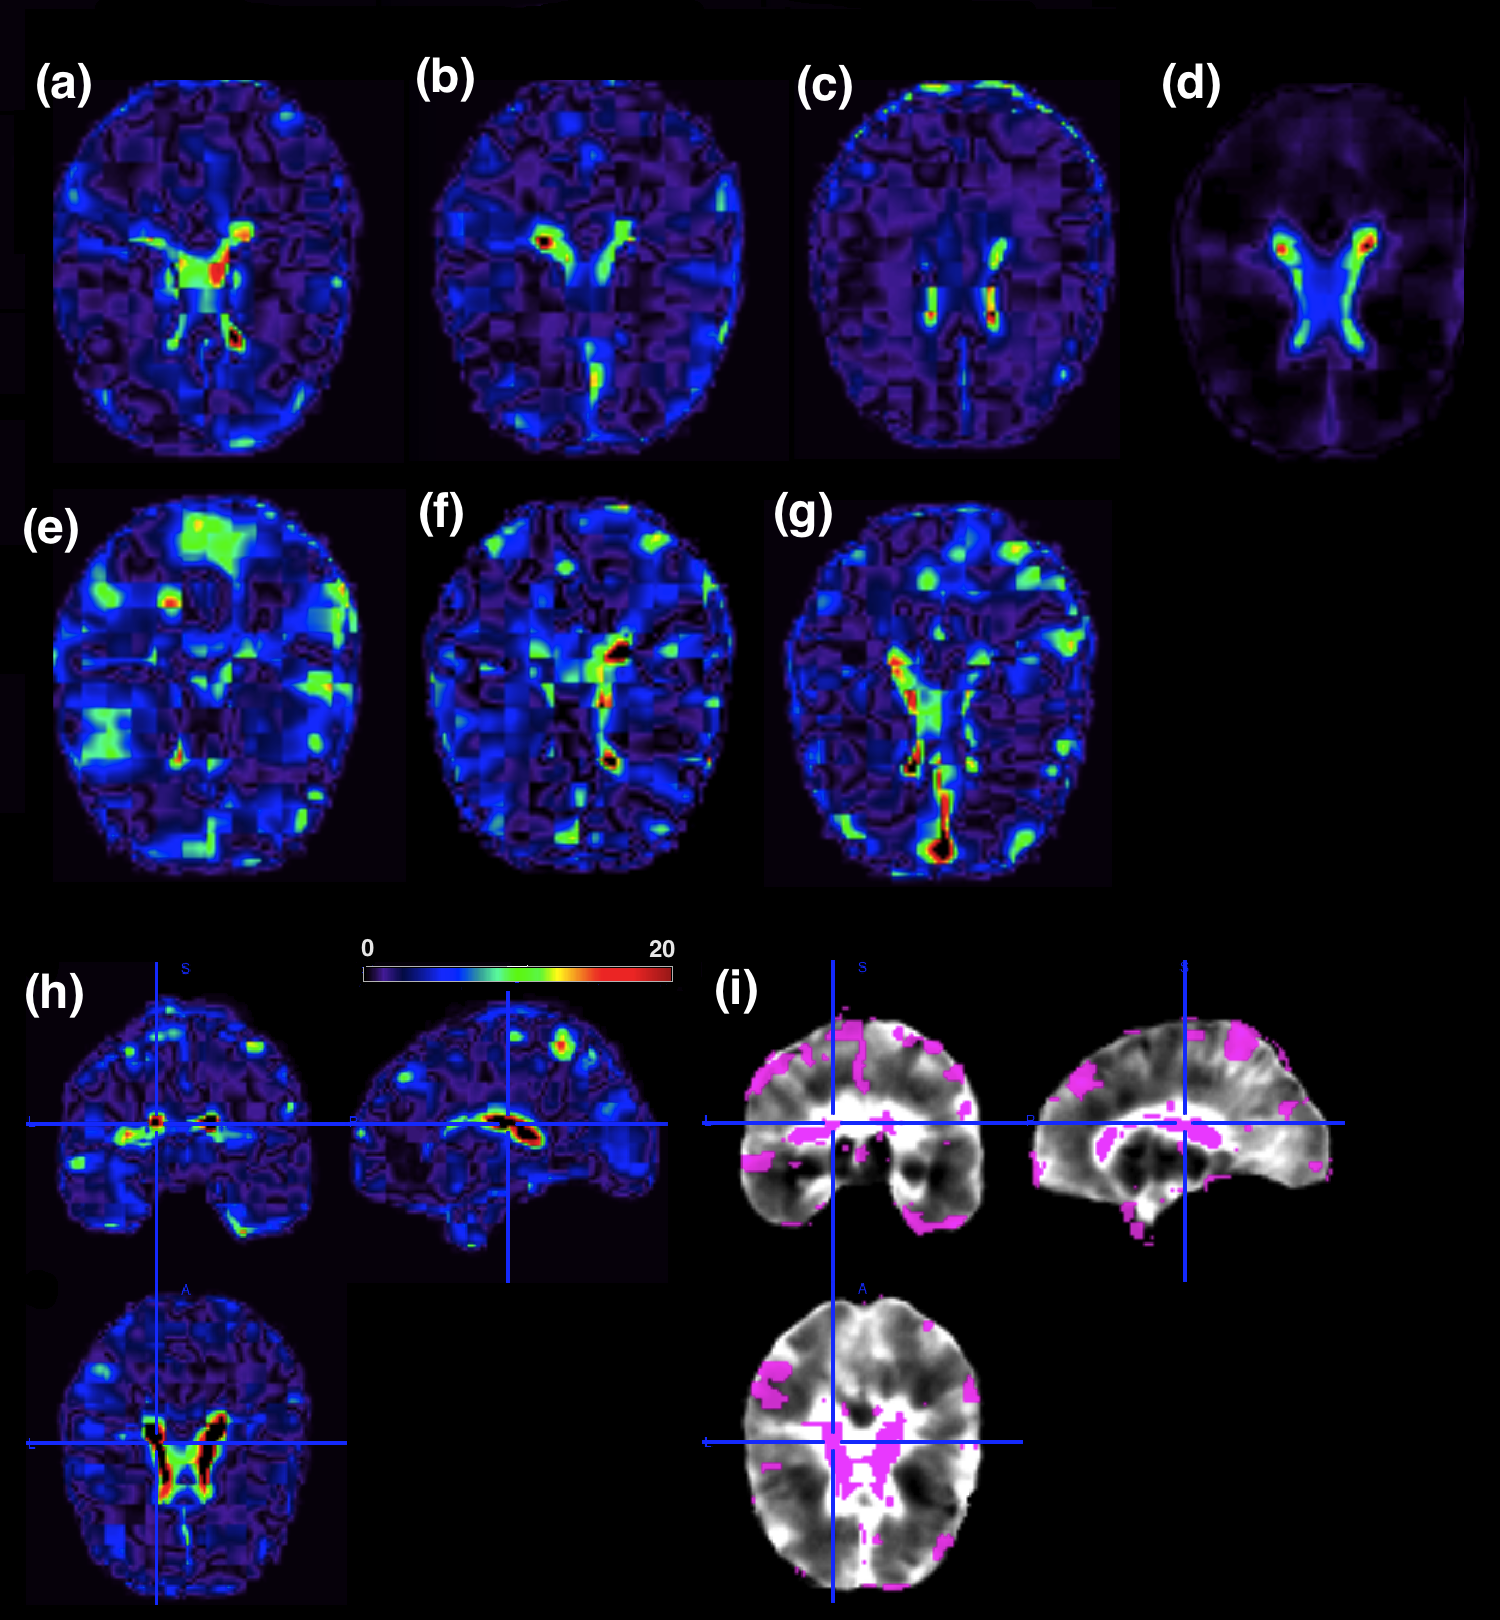

Based on the prediction accuracy, we selected the model with all partitions of size 6×6×66666\times 6\times 6 mm3superscriptmm3\mbox{mm}^{3} and R=5𝑅5R=5. For the selected model, we fitted TPRM with σ2=104superscript𝜎2superscript104\sigma^{2}=10^{4}, ϵ=104italic-ϵsuperscript104\epsilon=10^{-4}, and α0π=α1π=0.5subscript𝛼0𝜋subscript𝛼1𝜋0.5\alpha_{0\pi}=\alpha_{1\pi}=0.5 to reflect the bathtub prior. In the first screening procedure, we eliminated the partitions whose features, extracted from the tensor decomposition, are zero because they are not relevant in the prediction of AD. From the 4,096 original partitions, only 1,720 passed the first screening, totaling 8,600 features. Figure 4 shows the correlation between the features extracted in the first screening step. Inspecting Figure 4 reveals high correlations between features within most partitions and across nearby partitions. Thus, adding the third component of TPRM can reduce correlation in the selected features.

Finally, we run the Gibbs sampler algorithm described in Section 2.4 for 150,000150000150,000 iterations with a burn-in period of 5,00050005,000 iterations and thining interval of 50. Based on a 95%percent9595\% credible interval corrected by the number of test using Bonferroni (α=0.05/50𝛼0.0550\alpha=0.05/50), we considered seven components to be important for predicting AD outcome. Convergence plots for the 7 coefficients and their correspondent qqplots are shown in Figure 9 of Appendix D. Panels (a) to (g) of Figure 5 present an axial slice of the 7 important features represented in the image space in their order of importance. The importance is quantified by the absolute value of the posterior mean for each selected feature. We also present a sensitivity analysis for the hyperparameters α0πsubscript𝛼0𝜋\alpha_{0\pi} and α1πsubscript𝛼1𝜋\alpha_{1\pi} and conclude that the selected features are consistent across different combinations of these hyperparameters. Results are included in Appendix C.

Refer to caption

Figure 5: ADNI data analysis results: panel (a)-(g) show an axial slice of the most important bases projected into the image space. The importance is given by the absolute value of the posterior mean in each one of the 7 selected features. Panel (h) shows the results for the absolute value of the projection 𝒫𝒫\mathcal{P} for the ADNI dataset. Colors on the right side of the colorbar indicate regions where differences are higher between the control group and the Alzheimer’s group. Panel (i) shows a threshold of 𝒫𝒫\mathcal{P} with colored parts indicating the biomarkers used to predict the onset of AD.

Second, let 𝒑~=𝒃^T𝑫~𝒑superscript^𝒃𝑇𝑫\tilde{{\mbox{\boldmath${p}$}}}=\hat{{\mbox{\boldmath${b}$}}}^{T}{{\mbox{\boldmath${D}$}}} be a 1×PL1subscript𝑃𝐿1\times P_{L} vector representing the estimated coefficient vector 𝒃^^𝒃\hat{{\mbox{\boldmath${b}$}}} in the local image feature space spanned by the columns of 𝑳𝑳{L}. We computed the projection 𝒫=Λ;𝑨(1),𝑨(2),𝑨(3),𝒑~\mathcal{P}=\|\Lambda;{{\mbox{\boldmath${A}$}}^{(1)}},{{\mbox{\boldmath${A}$}}^{(2)}},{{\mbox{\boldmath${A}$}}^{(3)}},\tilde{{\mbox{\boldmath${p}$}}}\|. The projection 𝒫𝒫\mathcal{P} is a representation of the estimated coefficient vector 𝒃^^𝒃\hat{{\mbox{\boldmath${b}$}}} in the three-dimensional image space. Panel (g) of Figure 5 presents the absolute value of 𝒫𝒫\mathcal{P}, indicating regions of differences between the control group and the Alzheimer’s group. Values on the right hand side of the colorbar are the regions where differences between AD and controls are high. To highlight these biomarkers, we thresholded 𝒫𝒫\mathcal{P} to reveal some of the important regions for AD prediction (Panel (h) of Figure 5). The threshold value was chosen to select the 5%percent55\% highest absolute values of the projection 𝒫𝒫\mathcal{P}.

To find specific brain locations that are meaningful for predicting AD, we label the signal locations and present it in Figure 5 based on the Jülich atlas (Eickhoff et al.,, 2005). The largest biomarker is the insula, as shown in Table 4, Appendix D. The insula is associated with perception, self-awareness, and cognitive function. Many studies have revealed its importance as an AD biomarker (Foundas et al.,, 1997; Karas et al.,, 2004; Jr. and Holtzman,, 2013; Hu et al.,, 2015). Other important biomarkers are located along the white-matter fiber tracts (fascicles), in particular a region known as the uncinate fascicle, which contains fiber tracts linking regions of the temporal lobe (such as hippocampus and amygdala) to several frontal cortex regions. Abnormalities within the fiber bundles of the uncinate fasciculus have been previously associated with AD (Yasmin et al.,, 2008; Salminen et al.,, 2013).

Another important biomarker is the hippocampus, which is associated with learning and consolidation of explicit memories from short-term memory to cortical memory storage for the long term (Campbell and MacQueen,, 2004). Previous studies have shown that this region is particularly vulnerable to Alzheimer’s disease pathology and already considerably damaged at the time clinical symptoms first appear (Schuff et al.,, 2009; Braak and Braak,, 1998). Other important biomarkers found by TPRM are shown in Table 4, Appendix D.